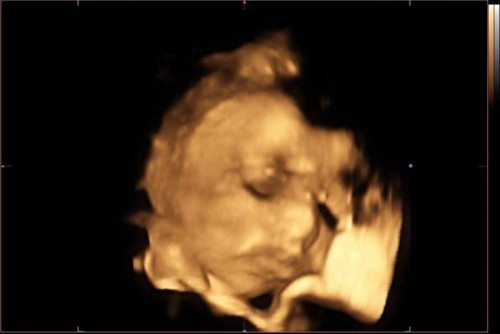

4d ultrasound π

Hi mga momsh π₯° share ko lang 4D results ng baby boy ko π naka two attempts kami sa kanya kasi hindi nagpakita nung una π€£ nahirapan tuloy ung doc sa kanya hahaha medyo na creeped out lang ako sa mata ng baby ko pero sabi ni doc nakamulat raw sya kaya ganyan ung mata nya, ano sa tingin nyo? Pakita narin sa 4d results nyo mga momsh π₯°